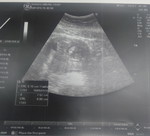

เราจะสามารถทราบเพศน้องได้ประมาณเดือนไหนค่ะ ท้องแรกค่ะ หมอจะซาวด์ให้เดือนไหนค่ะ

หมอนัดเดือนมกราคม ได้ประมาณ4เดือนเขาจะซาวด์ให้ไหมค้ะ

จะเห็นได้ชัดในวัยประมาณ 16w ค่ะ